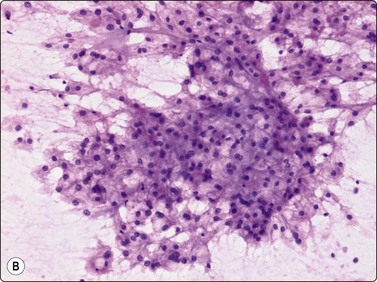

The giant cells have numerous (about 20–50) uniform nuclei. The spindle cells are mainly cohesive but single cells are always seen. The giant cells are typically attached to the periphery of clusters of spindle cells (Fig. 16.12A). Strands of collagen or basement membrane material, and endothelial cells are discernible in cell clusters and tissue fragments. The cells have a moderate amount of dense, amphophilic cytoplasm, which is often vacuolated, and well-defined borders. The nuclei vary only moderately in size and shape. They are ovoid, the chromatin is bland and nucleoli small (Fig. 16.12B). Malignancy (giant cell-rich osteosarcoma) should be suspected if spindled and multinucleated cells show nuclear pleomorphism and irregular chromatin, and if mitoses are plentiful. The differential diagnosis of other benign bone lesions with many osteoclastic giant cells such as aneurysmal bone cyst, osteoblastoma, brown tumor of hyperparathyroidism and reparative granuloma of jaw and small bones is difficult. Detailed knowledge of clinical and radiological findings is essential for a correct evaluation. The cytological appearance of giant cell tumor is recorded in a total of 38 cases in three series.3,19,20

image image

Fig. 16.12 Giant cell tumor of bone

(A) Tissue fragment of cohesive plump spindle or ovoid cells; giant cells located peripherally (H&E, IP).

(B) The nuclei vary moderately in size and shape, the chromatin is bland and nucleoli small (H&E, IP).